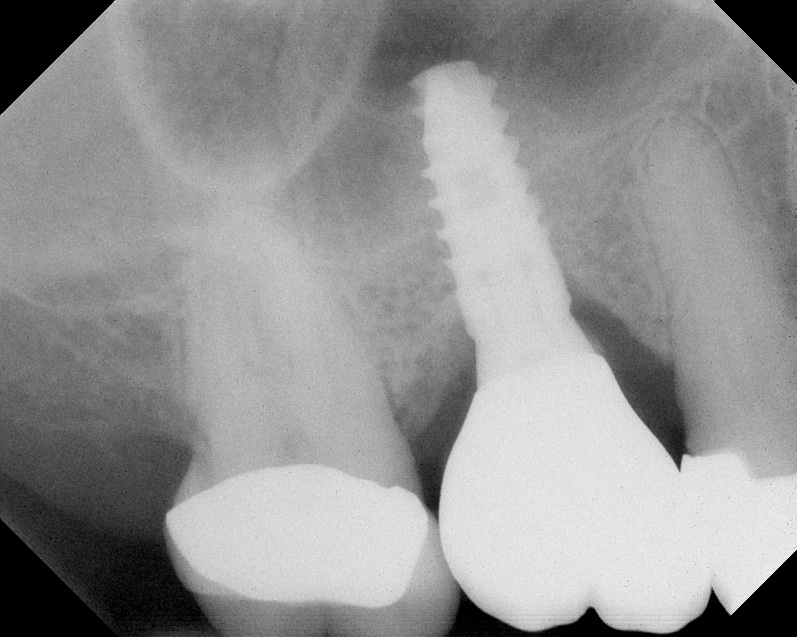

Radiograph of implant N o. 3 and sinus augmentation, day of placement. There is about 2 mm to 3 mm of native bone, and the sinus has been raised about 8 mm to 9 mm.

Fig. 10

The implant is then delivered and should be well stabilized in the bone. If there is any mobility of the implant, it can either be placed a little deeper (if there is enough native bone) or the implant can be removed and the procedure aborted, in which case it would be a two-stage procedure. This should rarely occur with the tapered designed implant, even with only 2 mm of native bone. Using a bone-level platform-shifting implant (or a tissue-level designed implant) is critical, as the hard and soft tissue will establish a biologic width. If an external hex type of implant is used and the shoulder is placed at the bone level, an expected bone loss of 1.5 mm to 2 mm will occur.24 Figure 10 shows proper bone-level implant depth placement with a platform-shifting design. In this case, a 3-mm healing abutment was placed at the time of surgery to avoid a secondary uncovering surgery, but an implant-level healing abutment could have been placed instead. As can be seen, there was only about 2 mm to 3 mm of native bone height. The membrane was raised about 8 mm to 9 mm. Comparing the radiograph on the day of surgery (Figure 10) to the 6-month postoperative radiograph (Figure 11) shows no loss of native bone, as well as the positive change in appearance of the grafted bone. The 3.5-month CBCT scan (Figure 12) shows good healing of the bone with no coronal bone loss. With minimal native bone present, as in this case, the use of a non-platform-shifting or non-tissue-level implant design could be problematic. After 1.5 mm to 2 mm of crestal bone loss, an external hex designed implant could develop instability with possible implant failure. If a non-tapered implant is used and bone loss occurs during healing, migration of the implant into the sinus could potentially occur. The surgeon can use either a healing abutment or implant-level closure screw over the implant shoulder. With patients who tend to use their tongues to explore or play with the area, or if the area is under a removable partial denture, a closure screw is recommended.